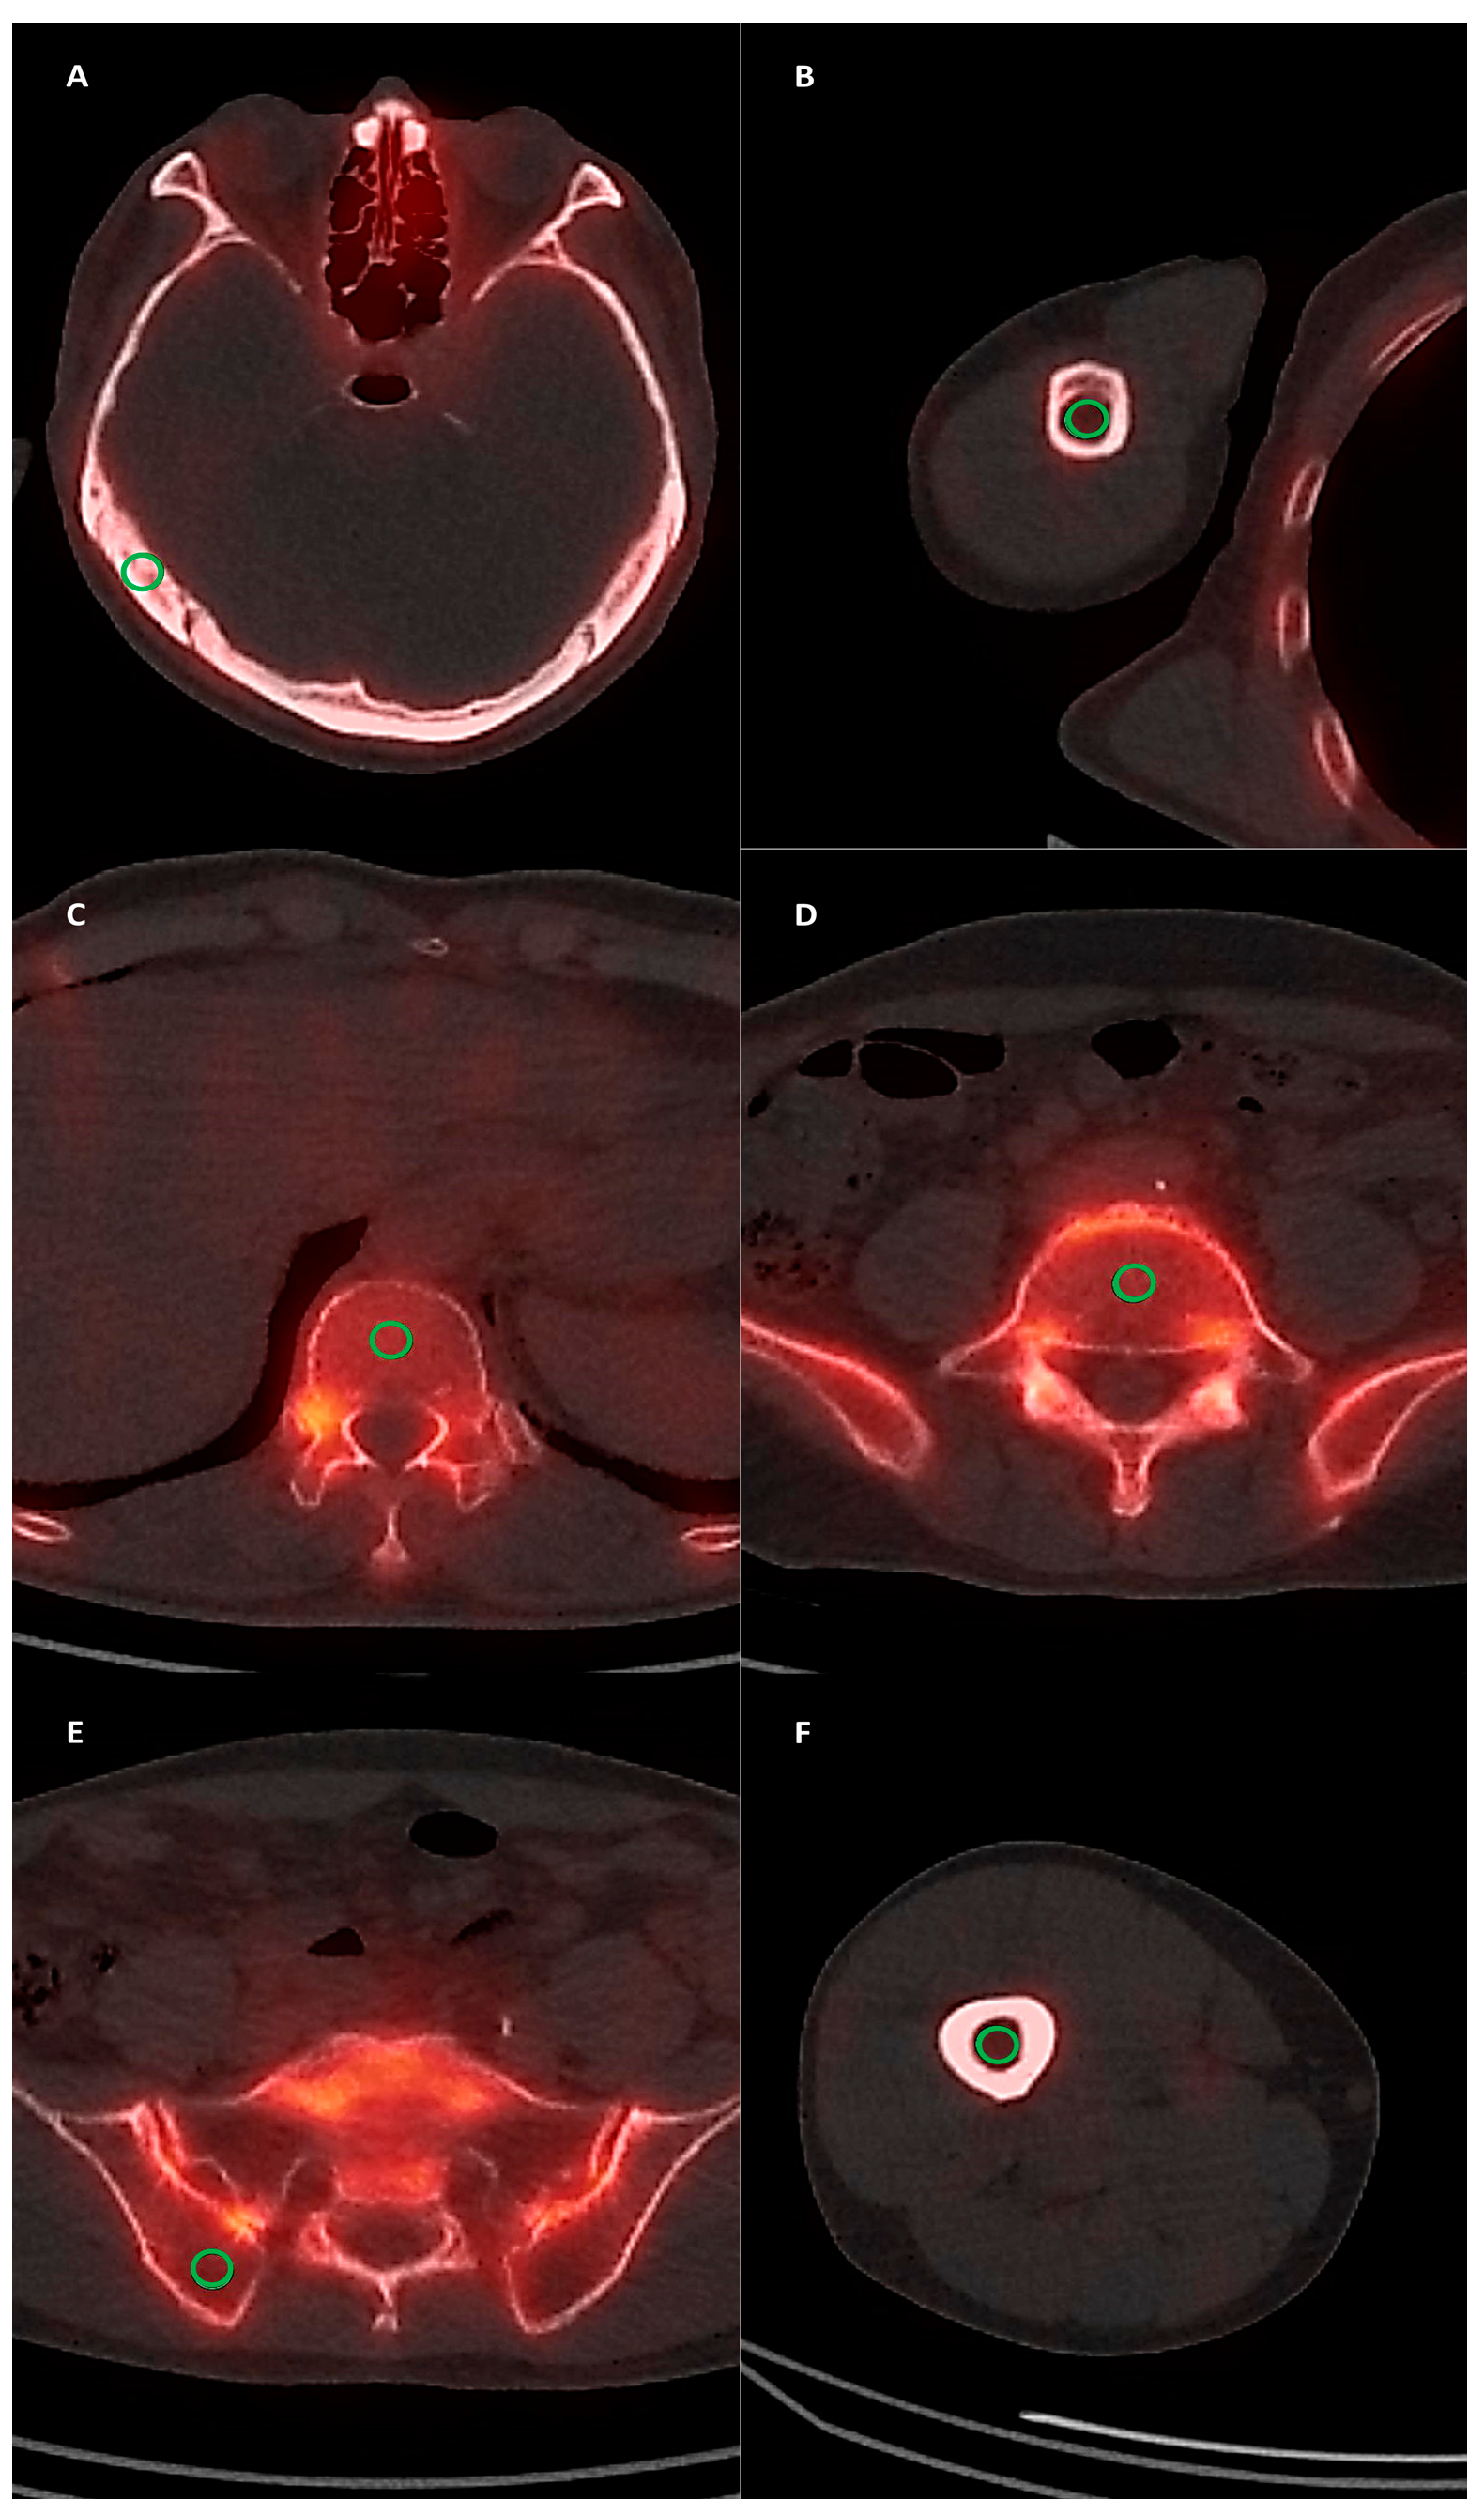

2.3. SPECT/CT Image Analysis

3.2. Normal Bone Uptake of SPECT/CT Images

3.3. Diagnostic Ability of SPECT/CT Imaging Parameters